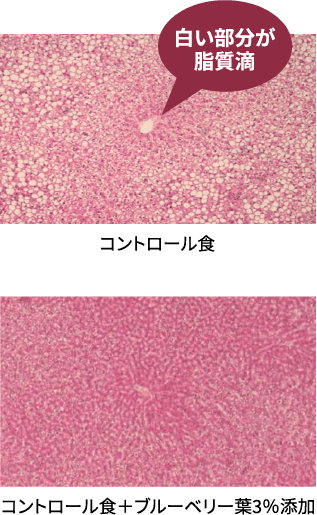

抗脂肪肝作用

ブルーベリー葉凍結乾燥粉末(飼料重量3%添加)をSDラットに30日間与えた場合、肝臓中の脂質量を抑える事がわかりました。

脂肪肝モデルラットの肝臓組織切片

肝臓切片に占める脂質滴の割合は、ブルーベリー葉の摂食により顕著な低下が認められました。

〔宮崎大学、宮崎県食品開発センターの

試験結果を引用〕ブルーベリー葉エキス末は

抗脂肪肝作用が期待できます -